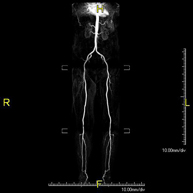

Prueba diagnóstica no invasiva que consiste en el estudio vascular del sector aorto-ilíaco y de los vasos arteriales de ambas extremidades inferiores, obteniendo imágenes de alta definición anatómica mediante el empleo de un campo electromagnético y ondas de radio (con un emisor y un receptor). Es indispensable el uso de contraste paramagnético (Gadolinio). Sin embargo, no utiliza radiación ionizante. La calidad de las imágenes permite realizar reconstrucciones en 2D y 3D. Está especialmente indicado en aquellos pacientes en los que hay sospecha de enfermedad vascular de ambas extremidades, en pacientes con enfermedad vascular de ambas extremidades como el mapa vascular antes del tratamiento (percutáneo o quirúrgico), como el mapa vascular pre-quirúrgico en pacientes con lesiones óseas o musculares que requieran cirugía, etc. - Angio-RM Arterias renales